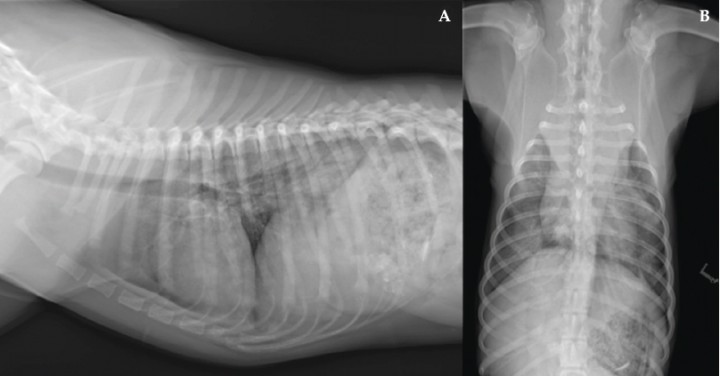

En este caso se optó por un tratamiento conservador, consiguiendo una evolución favorable, tal como se observa en las radiografías de control (Figs. 4 y 5). Aunque no se dispone de confirmación histopatológica, la evolución clínica y radiológica refuerza el diagnóstico de hematoma tímico, hemotórax y hemorragia pulmonar difusa.

<p>Radiografías realizadas a los 6 meses. (<strong>A</strong>) Proyección laterolateral derecha. (<strong>B</strong>) Proyección ventrodorsal. La resolución de los hallazgos radiográficos es completa.</p>

Radiografías realizadas a los 6 meses. (A) Proyección laterolateral derecha. (B) Proyección ventrodorsal. La resolución de los hallazgos radiográficos es completa.